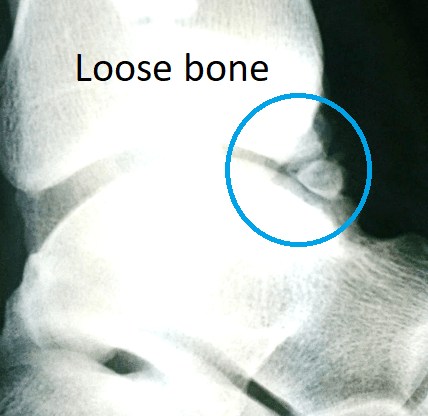

Causes include (see images below):

- scar tissue, adhesions and inflammation (synovitis)

- bone spurs from the tibia and talus bones

- loose bone fragment(s).

These investigations determine if the impingement is due to bone spurs, loose bone fragments, arthritis or just soft tissue scarring.